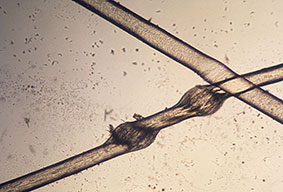

Trichoadenoma =ورم غدي شعري TRICHOADENOMA Trichoadenoma (of Nikolowski) is a rare follicular tumor that some authors consider a neoplastic process, whereas other authors consider it a malformation. These lesions occur most commonly in adults. Clinically, trichoadenoma presents as solitary, slowly growing, grayish nodules measuring up to 1.5 cm in diameter. They are mainly situated […]